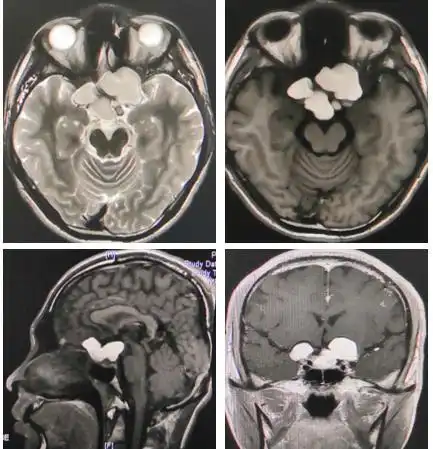

颅内长了"脂肪瘤"莫惊慌_脂肪瘤_症状表现_治疗方式_相关疾病 - 好